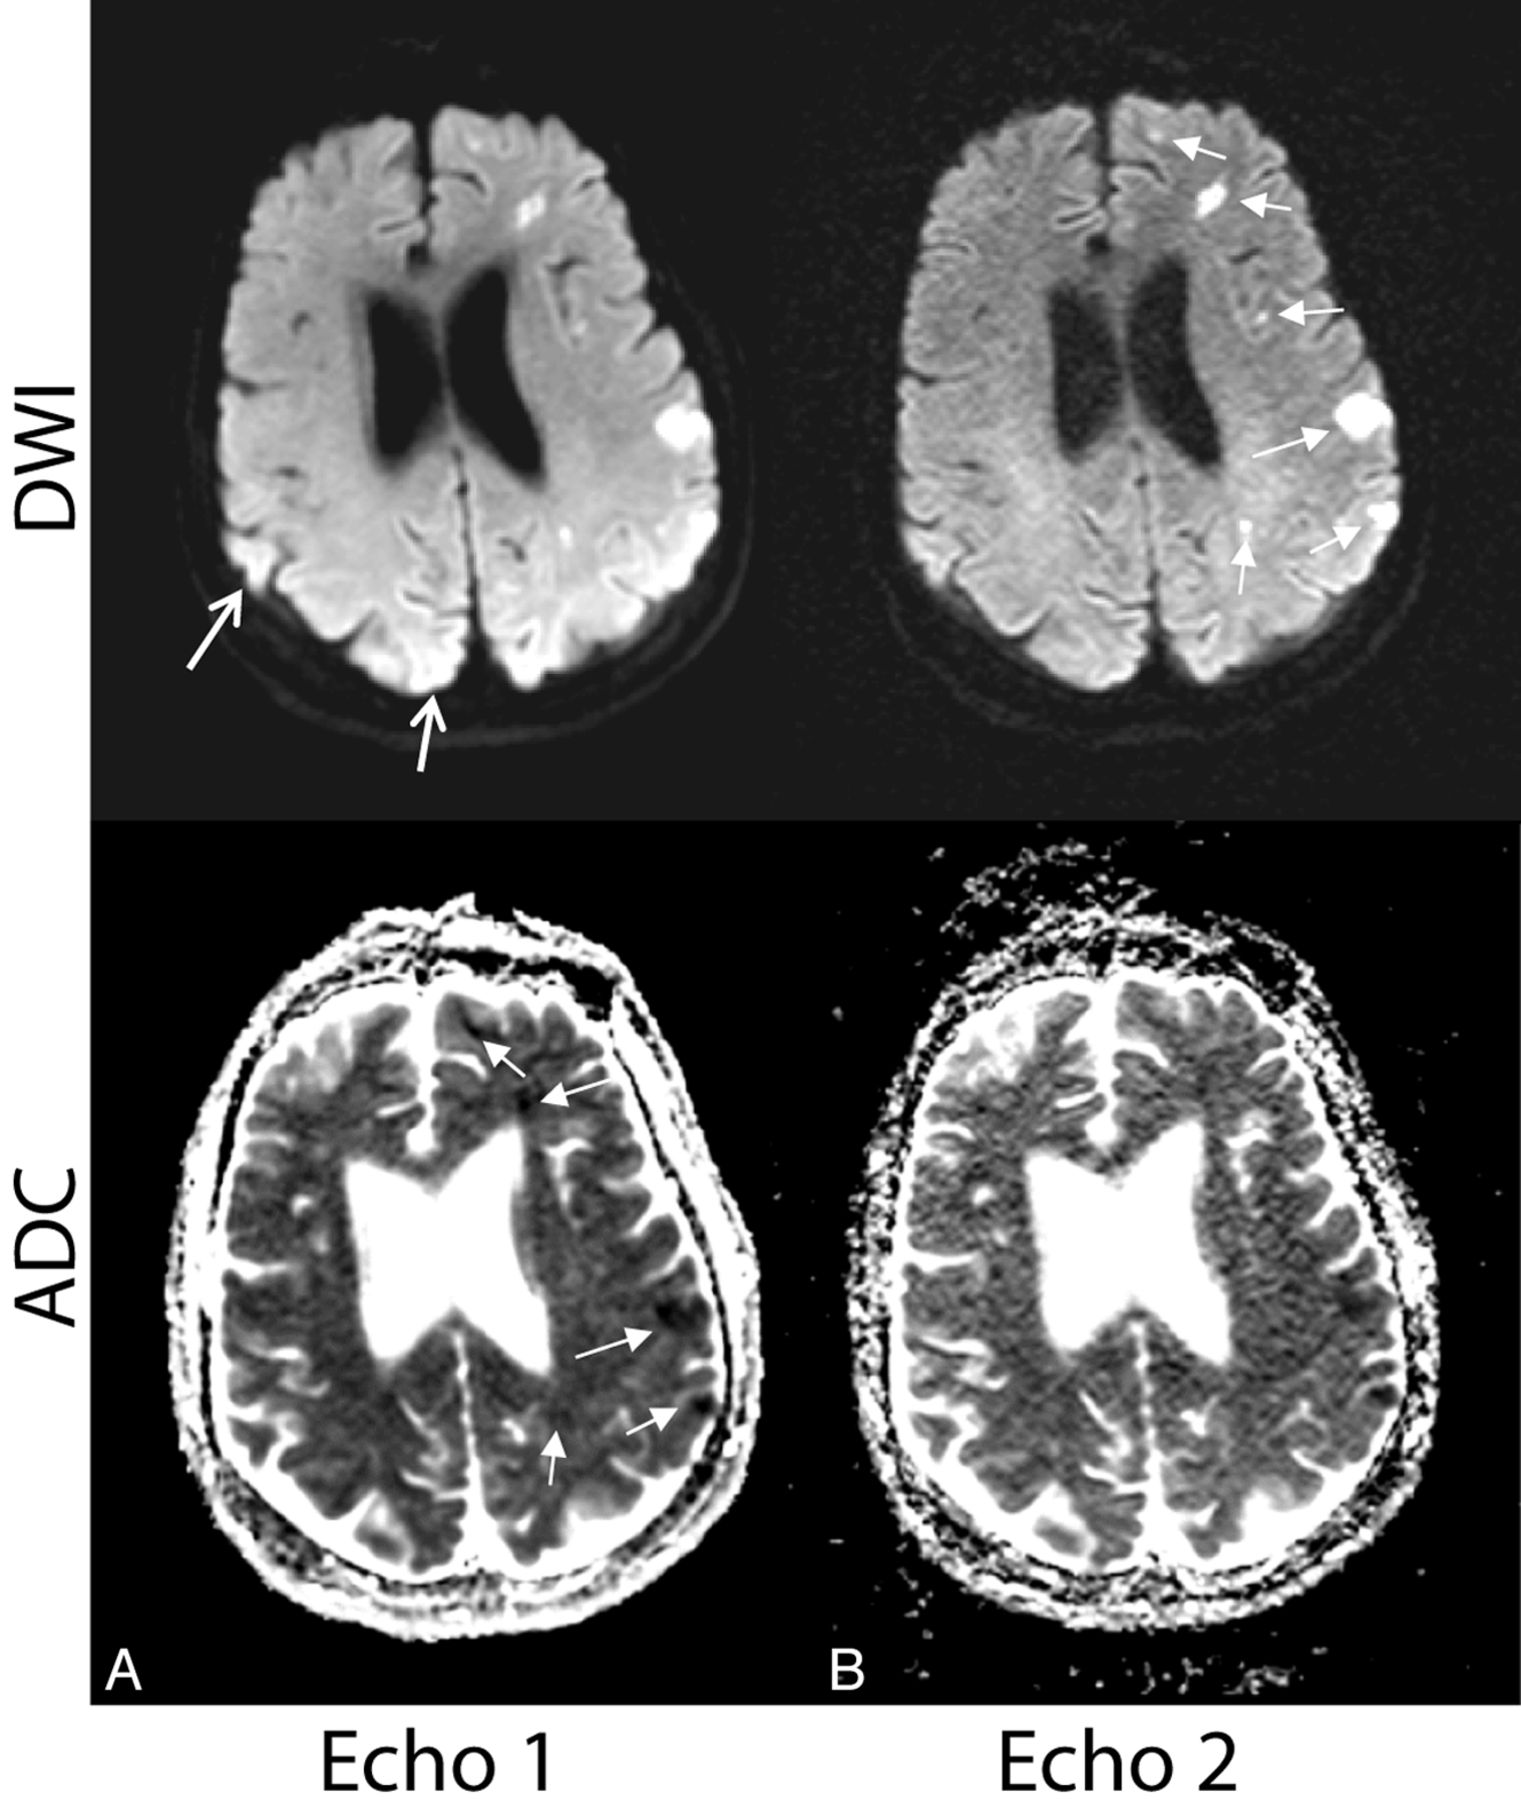

Figure 7 shows both echo 1 and echo 2 DWI and ADC of a patient with multiple embolic infarcts. Fourteen new lesions were found on the DWI of echo 2 in this patient, all of which were confirmed as lesions with decreased diffusivity on ADC of echo 1.

Case illustrating why echo 1 is more useful than echo 2 for calculating ADC maps used for the validation of acute infarct. Select images of a 66-year-old woman with embolic infarcts. DWI and ADC maps for echo 1 (A) and echo 2 (B) are shown. The DWI of echo 2 was found to have much higher sensitivity to acute lesions (confirmed on the ADC of echo 1) than echo 1. However, because the ADC of echo 2 is plagued by noise, echo 1 is considerably more useful for calculating ADC maps used for the validation of acute stroke (closed white arrows). The open white arrows represent areas where it can be difficult to rule out stroke from heightened coil sensitivity in (particularly posterior) regions of the brain.

Practical Considerations

While the DWI of echo 2 was considered superior to that of echo 1 in all measures apart from image quality, one must acquire a higher SNR echo 1 image to produce an ADC map to aid diagnostic specificity. Figure 7 shows echo 1 and echo 2 DWI and ADC maps of a patient with multiple embolic infarcts—illustrating the difficulty of decoupling noise from the infarct on the ADC of echo 2. Figure 7 also demonstrates that echo 2 can be more reliable in distinguishing infarct from heightened coil sensitivity present at the periphery of the image (particularly the posterior brain regions) on echo 1.